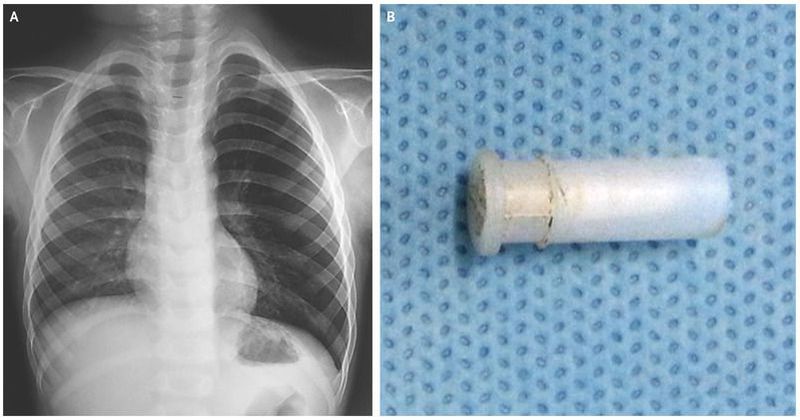

A 4-year-old boy presented to the otorhinolaryngology outpatient clinic with a 2-day history of persistent cough that had an intermittent whistling character The patient had no history or symptoms of viral infection of the upper respiratory tract, and he otherwise felt well. His parents reported that he had been playing with a whistle before the onset of his coughing. Physical examination was notable for an expiratory wheeze in the middle and lower left lung. The remainder of the physical examination was unremarkable. Radiography of the chest revealed hyperinflation of the left lung (Panel A). Although a foreign body could not be definitively identified, air trapping in expiratory radiographs can suggest the presence of an aspirated foreign body in the bronchus, since air can enter the bronchus around the foreign body but cannot exit. A rigid bronchoscopy was performed, given the likelihood that a foreign body had lodged in the lung. A toy whistle (Panel B), which had been obstructing the left segmental bronchus, was retrieved. A repeat chest radiograph, obtained the day after retrieval of the foreign body, showed resolution of the hyperinflation. The child remained well at a 1-year follow-up visit.